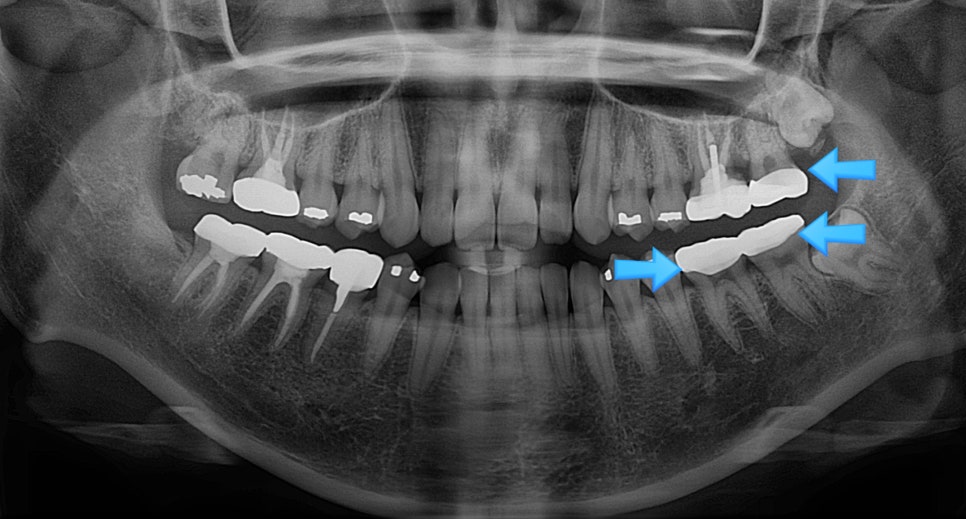

상악 교합면 사진 — 4개 치아에 아말감 충전물이 파란 화살표로 표시된 before 임상 사진

▲ 아말감으로 충치 치료를 여러 개 받으신 환자분의 상악 교합면